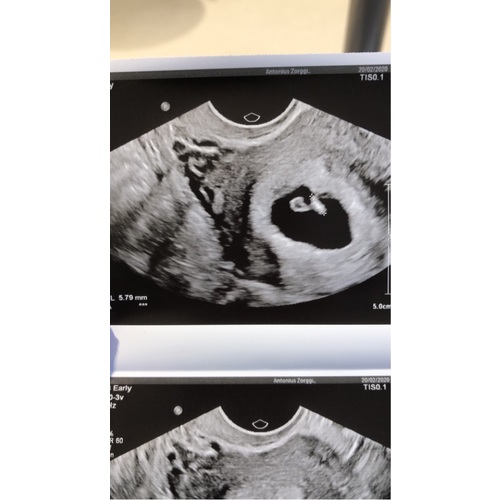

1e ronde clomid 50mg, met controles in het ziekenhuis, eitjes groeiden mooi ...